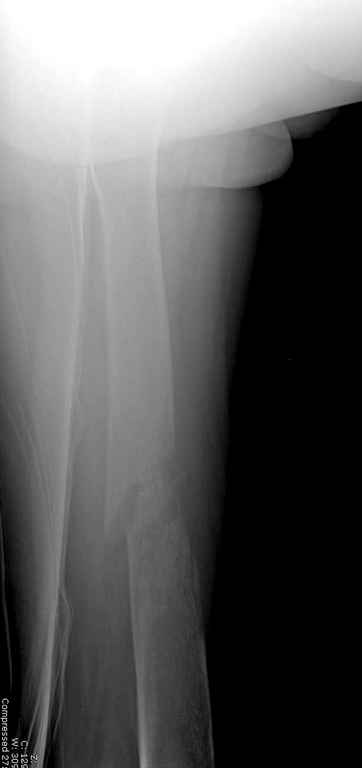

Здесь случай 66 летней пациентки со спонтанными болями в левой нижней конечности, обратилась в приемное, сделаны снимки бедра и КТ.

Патологический перелом бедра, конечность на вытяжении.

В зависимости от характера опухоли некоторые патологические переломы имеют риск кровотечения во время операции. Множественные литературные данные подтверждают, что надо проявить осторожность при интрамедуллярном остеосинтезе при неизвестных опухолях, особенно где имеется подозрение на Renal Cell Carcinoma. (RCC- hypernephroma) http://www.bonetumor.org/tumors/pages/page64.html

Со слов, больная ничем не болела, только последние 3 месяцев чувствовала боли в бедренной области. КТ брюшной полости подтвердил увеличенную правую почку. (5-6)